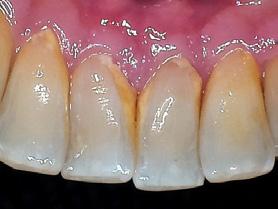

Dental hygienists independently utilize digital scanning for education and motivation. Not only can the clinician educate the patient with the images, but the patient has a visual that is easily understood. These images contain powerful visuals of attrition, fractured teeth, abfraction, gingival recession, overjet, and crowding.4 Biofilm can be displayed after the application of disclosing solution.5 Separate photos are not required to capture the biofilm present when using digital scanning.